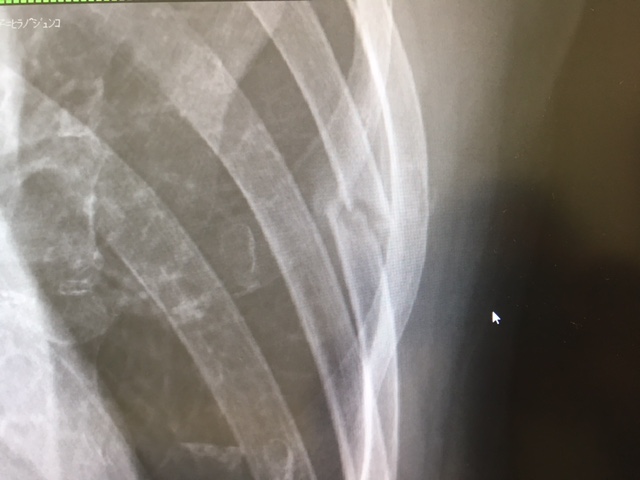

↓こちら、骨折直後。

パソコンのカーソルがあるところが5番目の肋骨で、見事にポッキリ・・・はい、折れてますねと。実は、このときにはわかりませんでしたが、右隣の4番目にも亀裂が入っていたもよう。当時は、くしゃみなどの特定の動作をした時に激痛。胸にゴムバンドみたいなものを巻いて動きを制限しつつ、鎮痛剤を飲み、湿布を貼って過ごす(涙)。